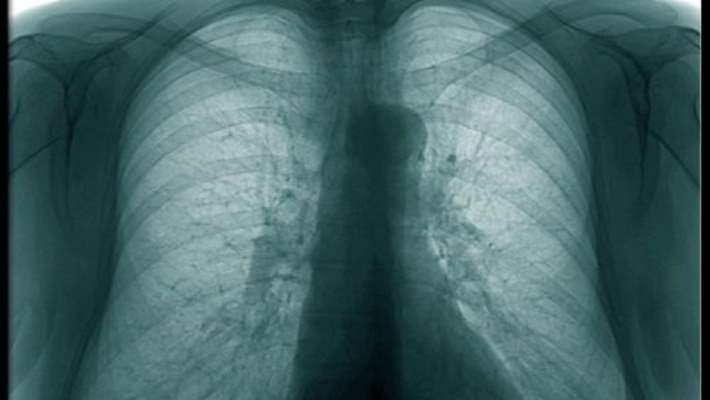

Bronşit hastalığında bronşun içi, bronşun zarı iltihaplanır. Yani şişer ve ödem haline gelir. Ödem denilen şişme durumu meydana gelir.

Bu arada sekresyon bezleri, mukus bezleri, bronşun balgam çıkartan bezleri aşırı derecede uyarıldığı için, bol miktarda sekresyon açığa çıkar.Bu bir bakıma hastalığın temizlenmesi için vücudun gösterdiği bir reaksiyondur. Fakat bu öyle şiddetli hale gelir ki, hava yolları daralmaya başlar. Şişmeden yani ödemden ve sekresyon artmasından dolayı hava yollarının çapı daralır ve solunum sıkıntısı başlar.

Böylece hava yolları havanın girmesine çıkmasına engel olmaya başlar. Bunun sonucunda da hastalarda öksürük ve nefes darlığı gibi yakınmalar görülür.